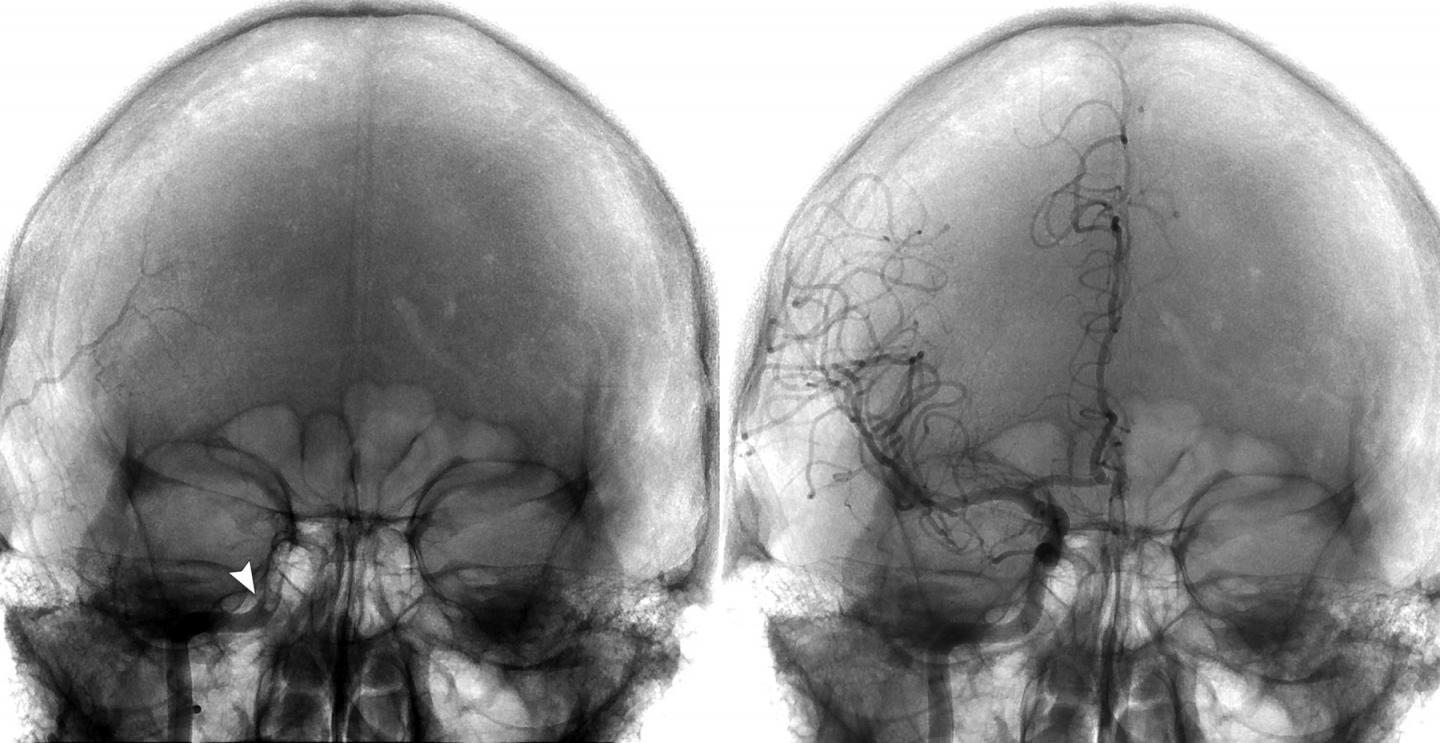

Brain Imaging -- Direct-Aspiration First Pass Technique Was Used to Remove a Large-Vessel Clot

Left: Frontal view of the skull showing occlusion of the right internal carotid artery (ICA) beginning at the level of the vertical petrous potion (arrow).

Right: Frontal view of the skull after thrombectomy shows the revascularization of the ICA and the distal arteries supplying the right side of the brain. view more